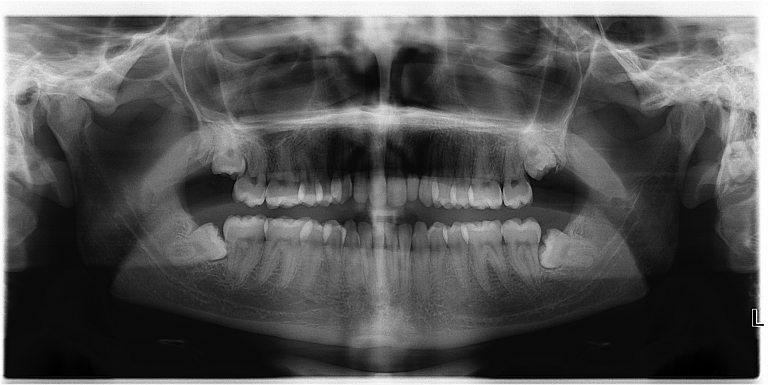

4. Răng khôn

![]() |

| Răng khôn không hề "khôn" như tên gọi của nó (Ảnh: Hack Spirit) |

Thời tiền sử, những chiếc răng khôn được sử dụng để nghiền thức ăn giúp cho con người dễ tiêu hóa hơn. Tuy nhiên ngày nay, việc con người chuyển sang ăn những thực phẩm được nấy chín, cùng với đó là việc kết hợp dao nĩa khiến cho những chiếc răng khôn này trở nên vô tác dụng. Đáng ghét hơn, những chiếc răng khôn này còn khiến cho chúng ta bị đau, làm xô lệch hàm răng khi chúng mọc lên.